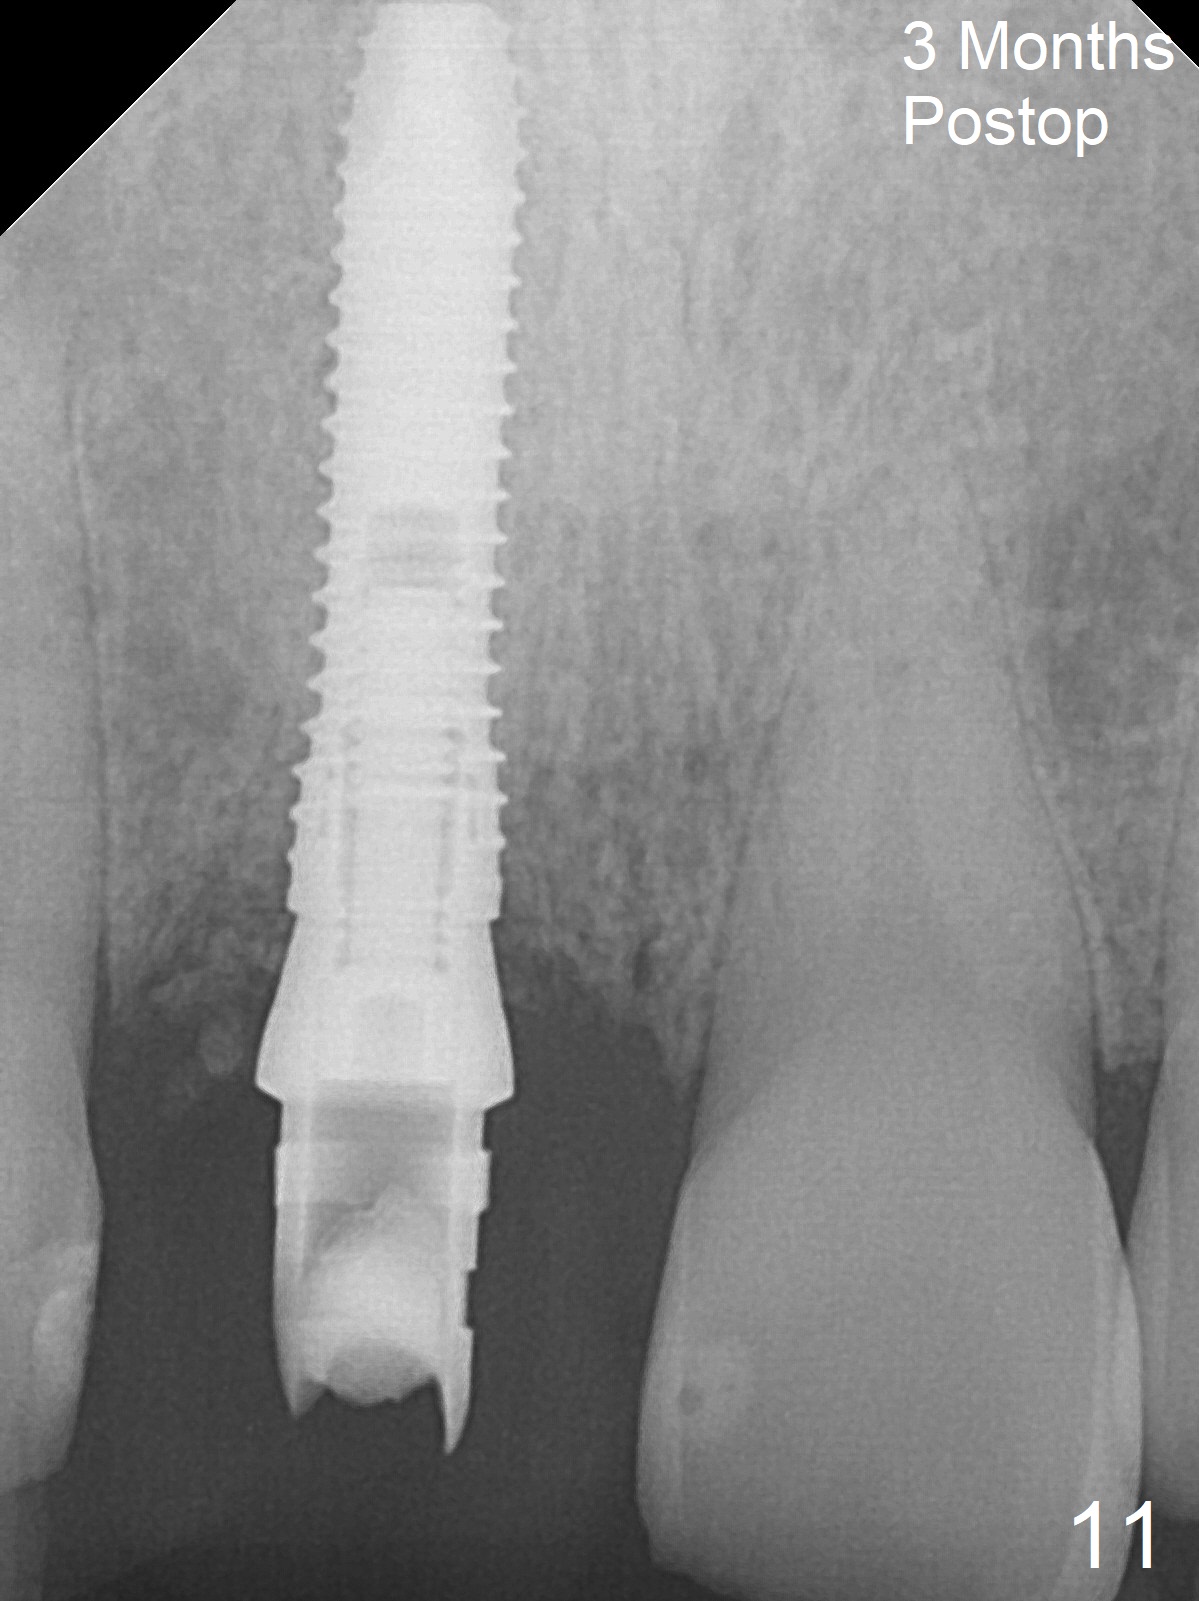

The buccal gingiva at #8 is erythematous (Fig.1: *), which is associated with the tooth fracture line (Fig.2 with granulation tissue: *). The buccal plate remains intact. Osteotomy is initiated in the palatal wall of the socket (Fig.3,4). The initial osteotomy depth is 16 mm (Fig.5); the trajectory is going to be adjusted as shown by arrows. The trajectory improves when a 3.8x15 mm dummy implant is placed (Fig.6). The definitive implant (3.8x16 mm) appears to be placed at an appropriate level (Fig.7). A 4.5x3 mm temporary abutment is inserted for an immediate provisional. As routine, Vera Graft is placed in the buccal gap. The buccal gingival erythema reduces without tenderness 1 week postop (Fig.8). Although the provisional is unstable, there is no bone loss 2 months 20 days postop (Fig.9). Because of the loose provisional (partial detachment from the underlying temporary abutment), impression is taken earlier (3 months postop, Fig.10,11). Due to the pointed abutment tip, the crown is redone 3 times. By the time of cementation (nearly 5 months postop), the socket appears to have healed (Fig.12).